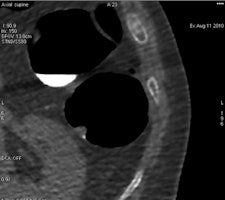

Optical colonoscopy (OC) is the gold standard for the detection and post-treatment follow-up of colorectal cancer. Its practice enables biopsy and treatment of polyps during the same session. But virtual colonoscopy (VC) offers specific advantages, such as the possibility of reviewing images repeatedly. VC is more comfortable than OC, and it enables the imaging of patients who cannot undergo a complete examination with colonoscopy due to stenotic changes or other technical difficulties. Depending on the specific case, VC can also be a good alternative in the case of low prevalence.

The modalities appear to be becoming increasingly complementary. Follow-up programs can also include VC in association with OC. In patients requiring prolonged follow-up, both methods can be interleaved for the detection of polyps or recurrence.